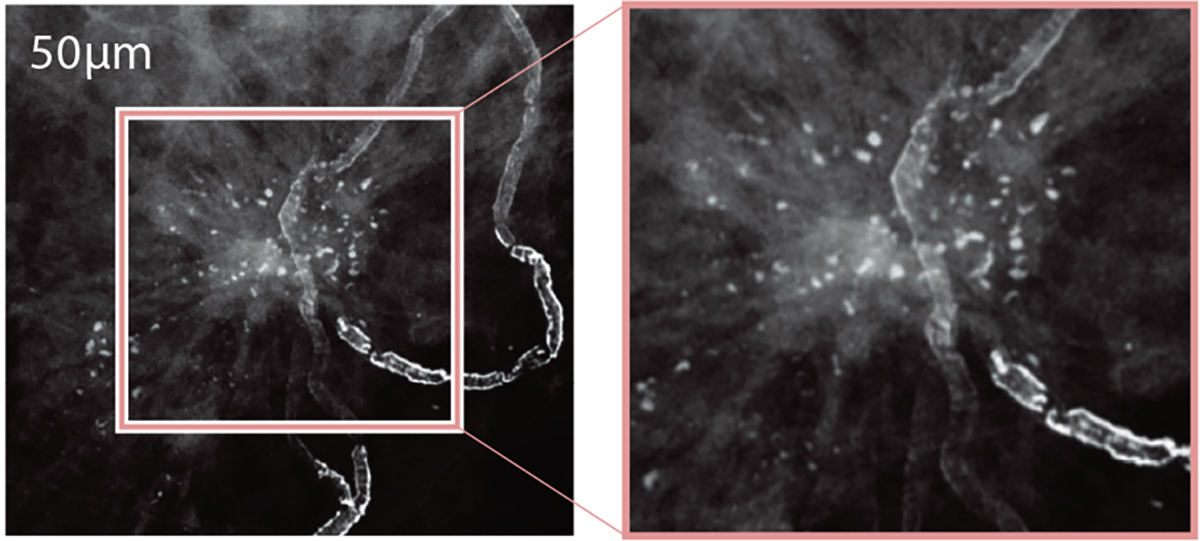

Biopsy Positioner - 50μm image solution

- Variable image resolution for different needs